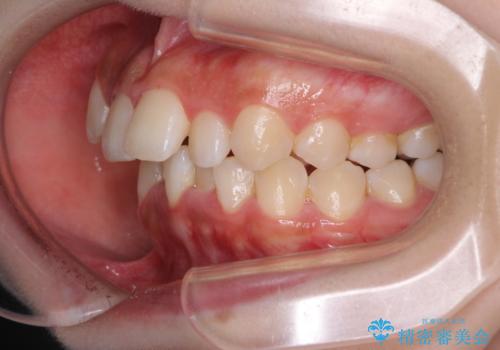

- 上顎の八重歯と、上下前歯のデコボコを気にして来院された患者様です。

奥歯の咬み合わせを見ると、上顎臼歯が下顎に対して前方にあり、叢生改善により口元が突出する顔貌ではなかったため、上顎左右第一小臼歯2本を抜歯し、ワイヤー装置にて矯正治療を行うこととしました。

前歯部のデコボコがなくなったため、歯磨きしやすくなり、非常に清潔な状態になりました。